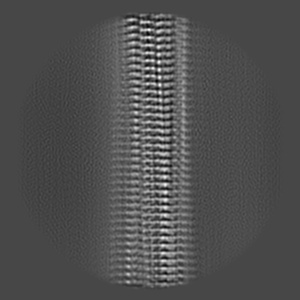

Cryo-EM structure of alpha-synuclein filaments from Parkinson's disease and dementia with Lewy bodies

Helical reconstruction2.2 Å

Sample: Alpha-synuclein filaments extracted from the human brain with PD, PDD, and DLB